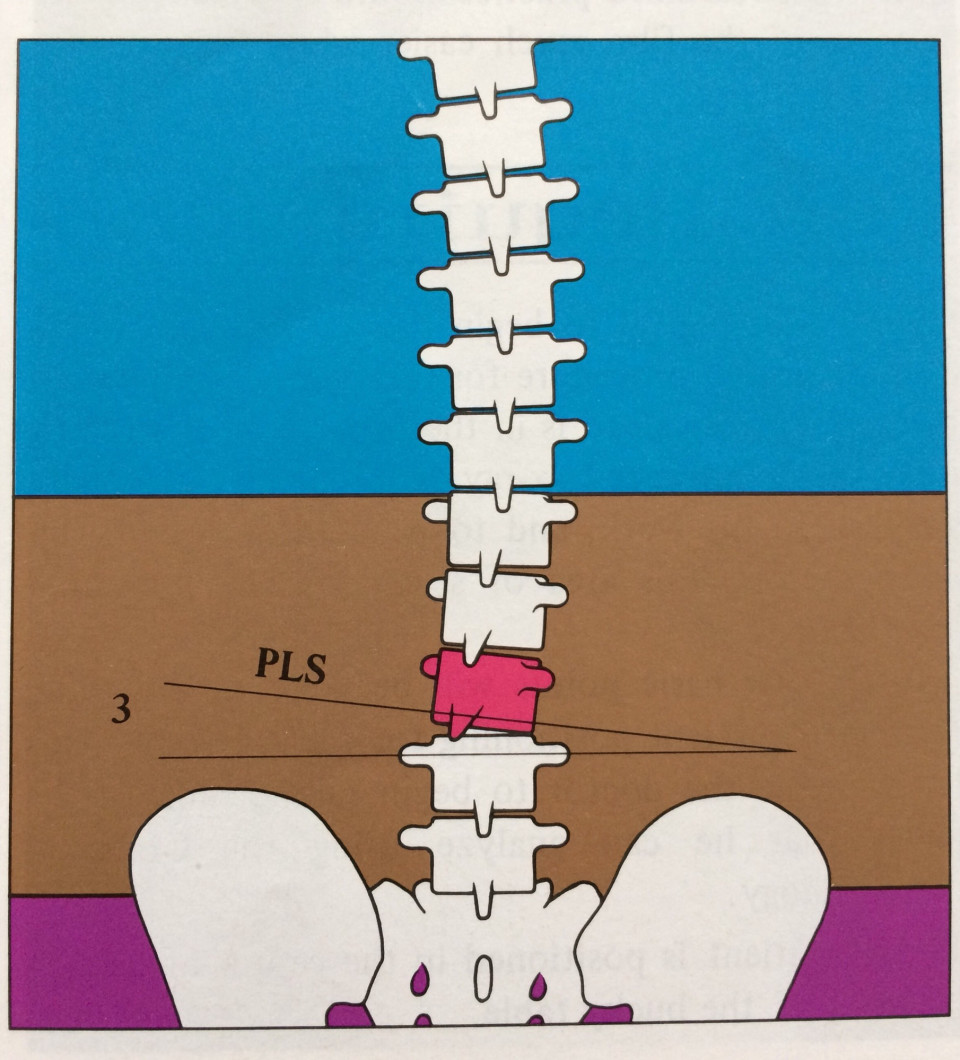

昨年の10月から週に1回のペースでアジャストメントを行ってきました。アジャストメントを行った箇所は、骨盤(腸骨や仙骨)、第6胸椎(T6)から第9胸椎(T9)、第7頚椎(C7)が中心でした。

昨年末の最後に1度だけ左の後頭骨(Occiput: PS-LS)に反応があったため、アジャストメントを行った時がありました。その後は、第7頚椎(C7)に戻り、現在まで上部頸椎のアジャストメントは行っていません。